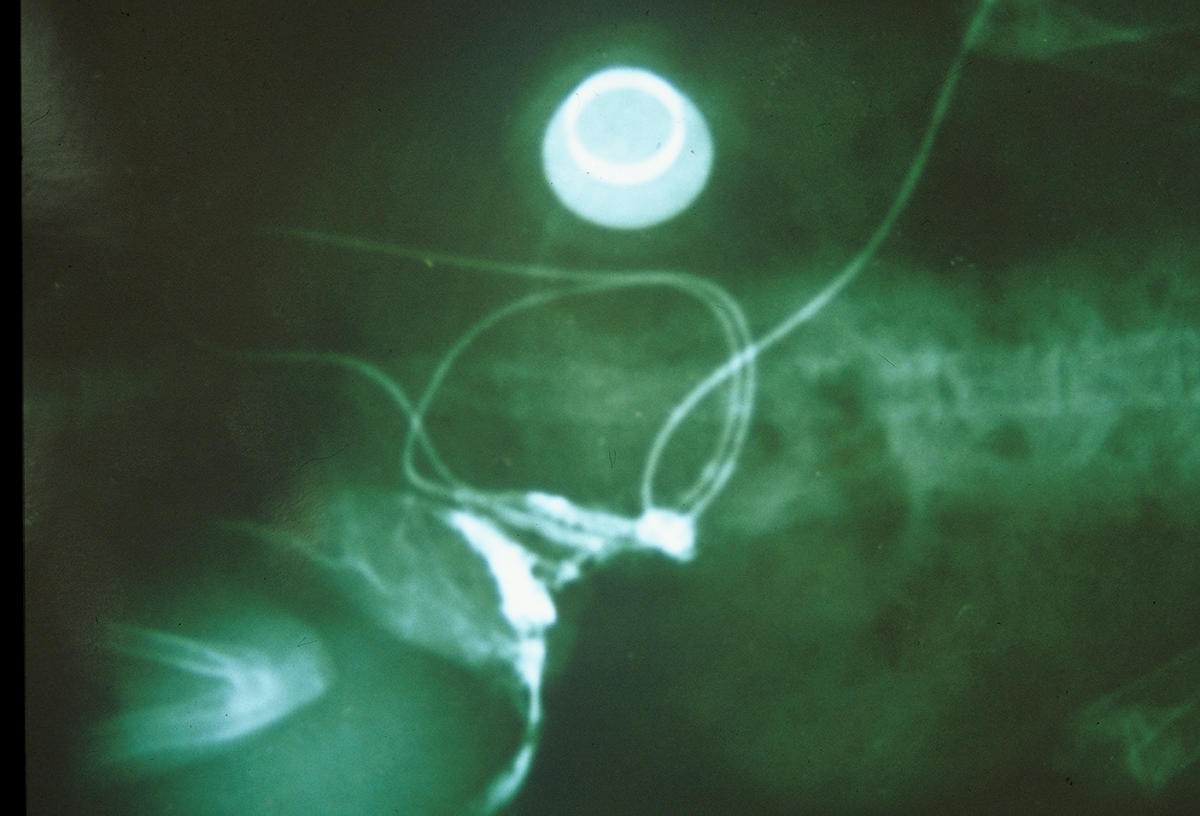

Figure 5From: Enhancement of Tissue Expansion by Calcium Channel Blocker: A preliminary studyX-Ray of the apparatus.Back to article page